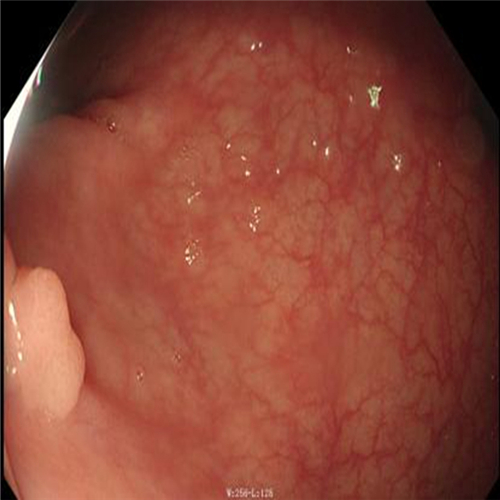

直腸息肉圖片

直腸息肉表現